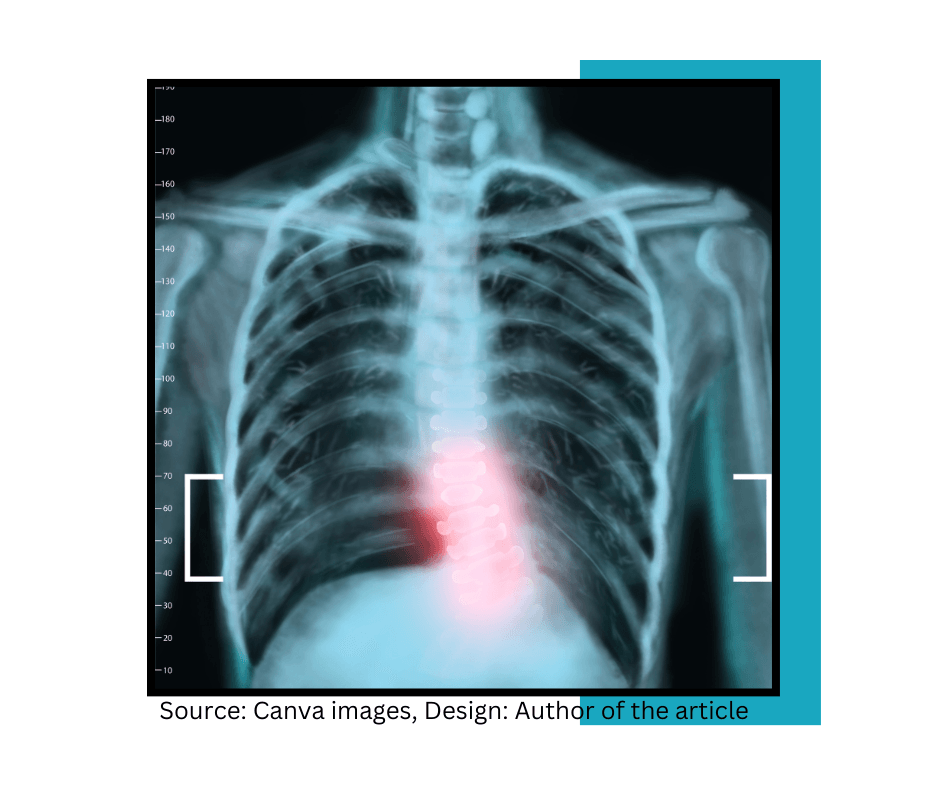

I explore scoliosis, chronic pain, disability, and inclusion through lived experience and neuroscience.

Each year, approximately 3 million new cases of scoliosis are identified. The majority are mild, requiring only regular monitoring by doctors.

Researchers at Washington University School of Medicine in St. Louis have discovered a potential link between the body's use of the mineral manganese and severe cases of scoliosis-a condition where the spine curves abnormally. Learn about early signs of scoliosis here.

Manganese is a trace mineral or micromineral. Although we don’t need a lot of it, it’s vital to get enough of it because your body requires it for many different processes. Researchers from Washington University School of Medicine in St. Louis found that Manganese plays a huge role in bone tissue formation suggesting that difficulties in processing this mineral might contribute to the onset of severe spinal curvature that we know as scoliosis.

The study found that children with severe scoliosis are twice as likely to carry a gene variant SLC39A8that hinders their cells from absorbing and utilizing manganese effectively.